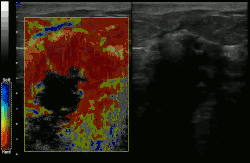

![]() Conventional ultrasonography (lower image) and elastography (supersonic shear imaging; upper image) of papillary thyroid carcinoma, a malignant cancer. The cancer (red) is much stiffer than the healthy tissue. | |

Elastography is any of a class of medical imaging diagnostic methods that map the elastic properties and stiffness of soft tissue.[1][2] The main idea is that whether the tissue is hard or soft will give diagnostic information about the presence or status of disease. For example, cancerous tumours will often be harder than the surrounding tissue, and diseased livers are stiffer than healthy ones.[1][2][3][4]

Supersonic shear imaging (SSI)

Supersonic shear imaging (SSI)[8][9] gives a quantitative, real-time two-dimensional map of tissue stiffness. SSI is based on SWEI: it uses acoustic radiation force to induce a 'push' inside the tissue of interest generating shear waves and the tissue's stiffness is computed from how fast the resulting shear wave travels through the tissue. Local tissue velocity maps are obtained with a conventional speckle tracking technique and provide a full movie of the shear wave propagation through the tissue. There are two principal innovations implemented in SSI. First, by using many near-simultaneous pushes, SSI creates a source of shear waves which is moved through the medium at a supersonic speed. Second, the generated shear wave is visualized by using ultrafast imaging technique. Using inversion algorithms, the shear elasticity of medium is mapped quantitatively from the wave propagation movie. SSI is the first ultrasonic imaging technology able to reach more than 10,000 frames per second of deep-seated organs. SSI provides a set of quantitative and in vivo parameters describing the tissue mechanical properties: Young's modulus, viscosity, anisotropy.

This approach demonstrated clinical benefit in breast, thyroid, liver, prostate, and musculoskeletal imaging. SSI is used for breast examination with a number of high-resolution linear transducers.[10] A large multi-center breast imaging study has demonstrated both reproducibility[11] and significant improvement in the classification[12] of breast lesions when shear wave elastography images are added to the interpretation of standard B-mode and Color mode ultrasound images.